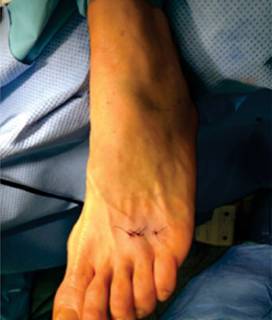

El paciente se colocó en decúbito supino bajo anestesia regional del pie y control por medio de fluoroscopio; se realizó primero la sección del ligamento intermetatarsiano con una hoja de bisturí 67 MIS, mediante una incisión longitudinal en el espacio intermetatarsiano a nivel del cuello (Figura 2), apoyándose sobre el cuarto metatarsiano, deslizándose sobre la cortical lateral con dirección inclinada de proximal hacia distal, se profundizó con la parte cortante hacia los dedos y con un movimiento de abajo hacia arriba se seccionó el ligamento intermetatarsiano transverso, percibiéndose el corte debido a la resistencia que se produjo en dicho acto.

El segundo gesto quirúrgico consistió en hacer osteotomías del tercer o cuarto metatarsiano usando dos incisiones a nivel del cuello, con la misma hoja de bisturí y a nivel del pliegue interdigital dorsal; con una raspa pequeña se disecó el periostio de la cara lateral del cuello del tercer metatarsiano y se hizo un canal a la vez; posteriormente, se introdujo una fresa Isham larga o Shanon 44 larga con una inclinación de 45º, se inició la osteotomía con una dirección oblicua de distal dorsal a plantar proximal (Figura 3). La osteotomía del cuarto metatarsiano se realizó de la misma forma. Se suturaron las heridas con nylon 3-0, se colocó un vendaje con gasas interdigitales de lateral a medial del segundo, tercer y cuarto espacios para estabilizar las articulaciones metatarsofalángicas; para finalizar, se puso un zapato postquirúrgico de suela rígida, que permitía el apoyo inmediato sin asistencia.